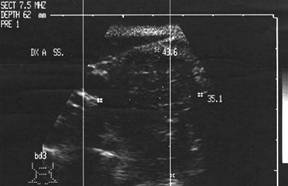

Carcinom papilar (recidiva localA)

Femeie de 36 ani. Cunoscuta cu maladie Graves. La un

an dupa prima tiroidectomie totala pentru neoplazie papilara multifocala cu

metastaze in ganglioni (pT4b N1 M0).

Mica formatiune nodulara medial de carotida dreapta (0,2 cc), marcat

hipoecogena.

Tireoglobulina: < 2 ng.

Examen citologic: carcinom papilar.

Aceeasi pacienta - hipervascularizatie interna la doppler color si powerdoppler

Aceeasi pacienta cu mica formatiune

nodulara medial de carotida dreapta - IRM